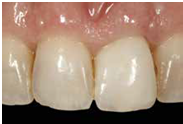

100/11/21 補綴完成

目前植體周圍的組織都很理想健康並追蹤中。